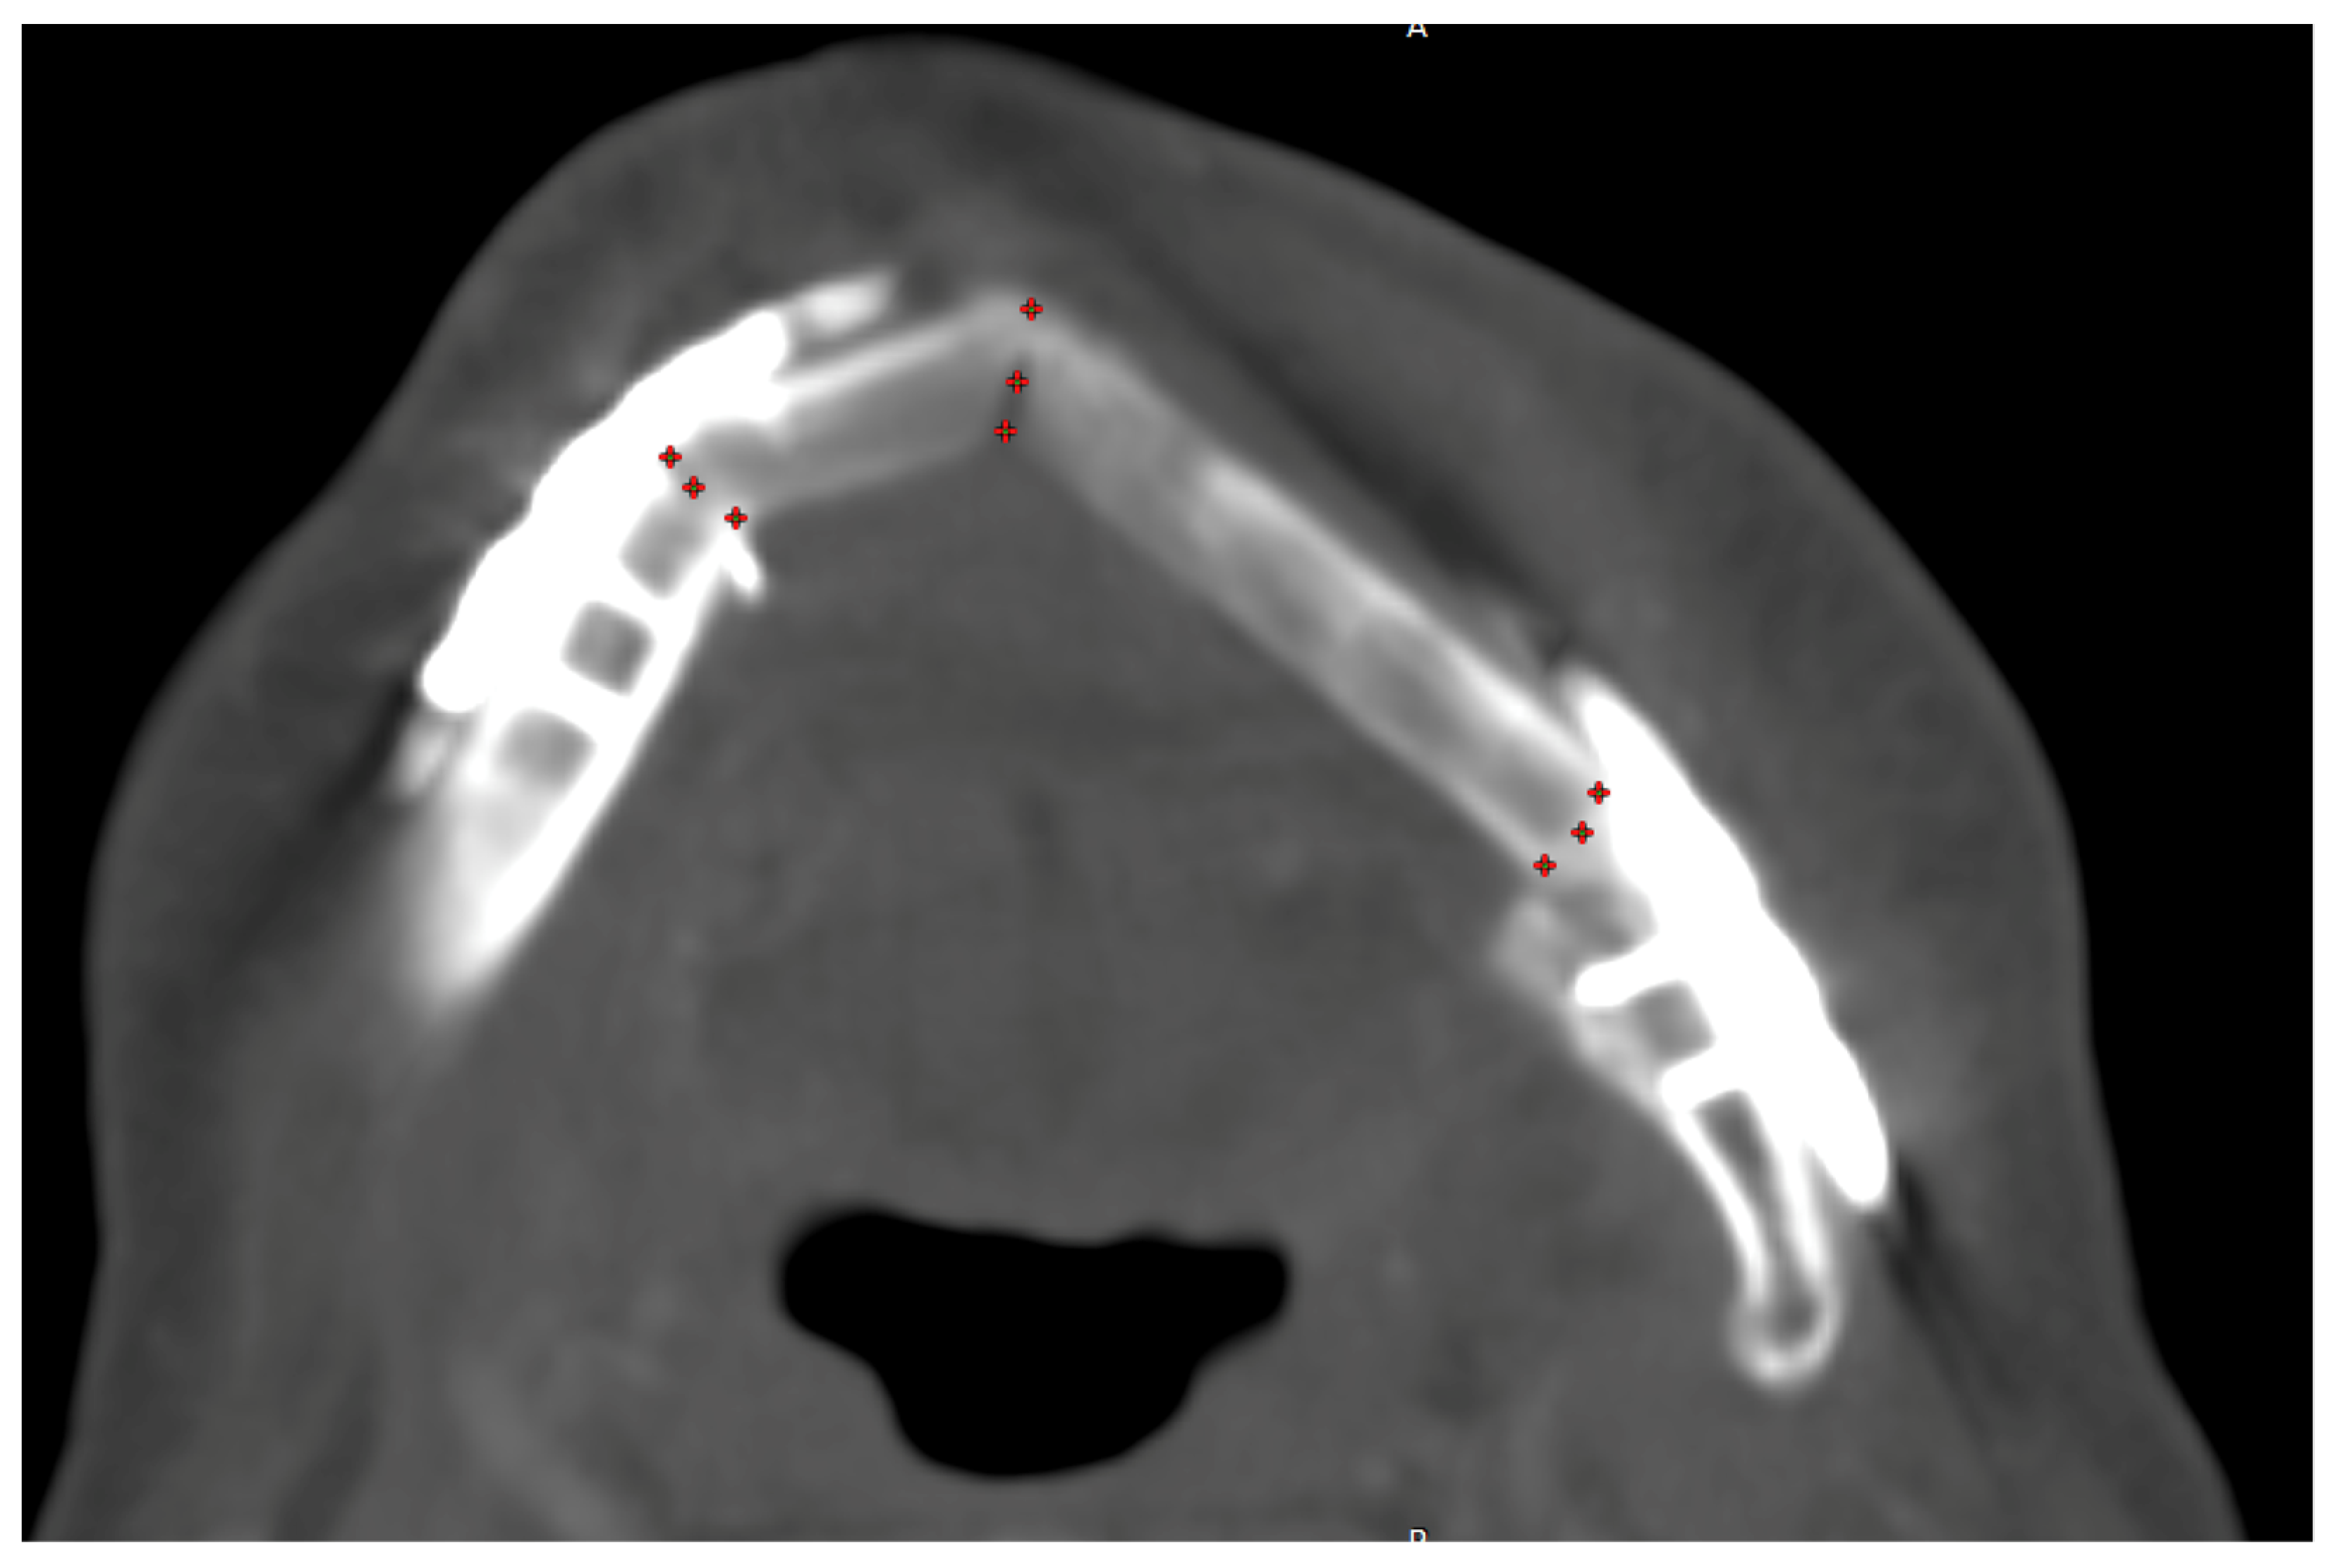

| HU gain overall for grouping locations horizontally #1 per day (p = 0.003) | ||||

| basal | reference | |||

| cranial | 5.26 | −53.34 | 63.86 | 0.860 |

| middle | 114.06 | 45.35 | 182.76 | 0.001 |

| HU gain overall for grouping locations vertically #2 per day (p = 0.005) | ||||

| Vestibular (+) | reference | |||

| Lingual (*) | −98.72 | −157.31 | −40.13 | 0.001 |

| Middle (#) | −86.70 | −155.41 | −17.99 | 0.013 |